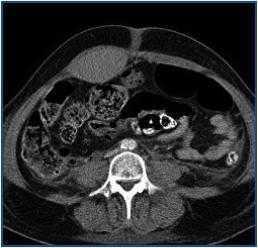

Treatment with methylprednisolone, cyclophosphamide and plasmapheresis (anticoagulation with citrate and replacement initially with albumin and later combined with plasma). Deterioration of renal function persisted with creatinine of 8.4mg/dL and oliguria. Haemodialysis without heparin was begun. After thirteen days the patient complained of pain in the hypogastrium and left iliac fossa following a coughing episode. An abdominal mass and anaemia of four points were apparent. An abdominal CT revealed a haematoma of the left anterior rectus sheath (figure 1). Three concentrates were transfused. A coagulation test including factors was normal except for an Ivy value of ten minutes. Three days later there was new pain in the right iliac fossa, with paralytic ileus and anaemia of three points. A CT revealed a haematoma in both anterior rectus muscles which extended towards the Retzius space and pelvis (figure 2). It pinpointed four concentrations of erythrocytes. The departments of surgery and interventional radiology consulted, deciding on conservative expectant treatment and associating antibiotics (clavulanic amocycillin) as well as parenteral nutrition.

Figure 2.